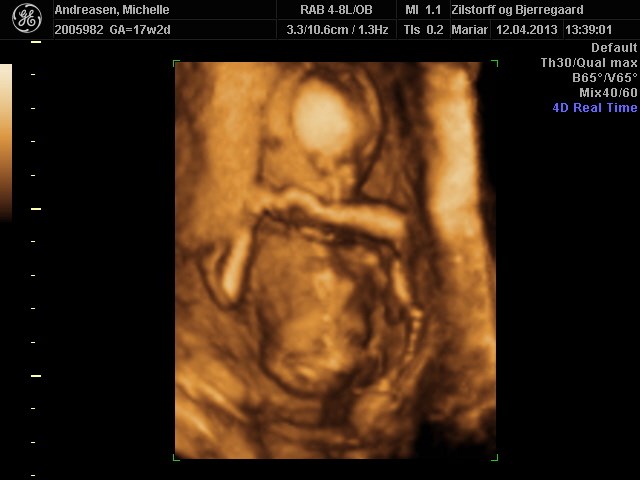

Her er nogle billeder af vores pige 17+2

Vedhæftede fotos (klik for at se i fuld størrelse)